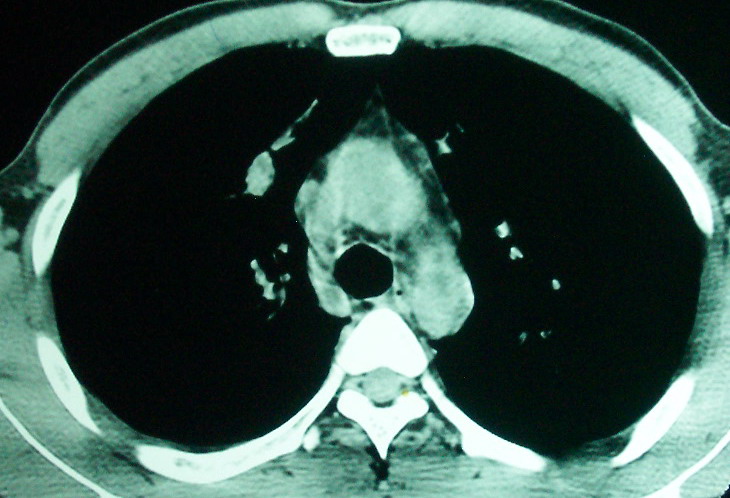

m      37y      发热   咳脓痰月余      ct肺脓肿但住院抗炎治疗后双肺内结节不知该如何解释

治疗后见左肺下野病灶较前缩小但双肺内结节影似无变化请较各位老师该如何下结论    治疗前wbc14.5 治疗后wbc 11.0

血源性肺脓肿,一般由原发感染灶引起脓毒败血症,在肺部形成小脓肿,病变变化快,容易形成肺气囊,脓气胸,主要与转移瘤鉴别,通过临床病史可分

结合病史考虑血源性肺脓肿,与转移瘤鉴别

空洞内可见小结节样密度影考虑合并真菌感染

结合临床发热,咳痰考虑为血源性肺脓肿,不过双肺结节又在肺的边缘,还是小心一点,抗炎后复查吧

左下肺病灶除了明显的厚壁空洞 气液平外,明显见壁结节,另两肺多发小结节,综合考虑:左下肺周围性肺癌伴肺内转移.

如果你仔细的同层面对比,你会发现所有的病灶均有比较明显的吸收、缩小。病变的形态,特别是脓肿的形态、壁的厚薄、内壁均有很大的变化,均在往好的方面发展。与临床症状、血像均符合,治疗效果比较显著,就是肺脓肿并双肺的化脓性炎症灶。